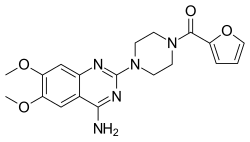

| Prazosin | Minipress |

|

Inverse agonist of α1 receptor.[10] | Lowers blood pressure.[2] | ||